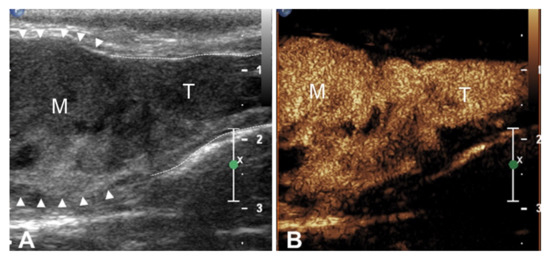

| 1 | Thyroid carcinoma | Thyroid veins (right and left) | 2 Hyperechoic nodules (left: 2.8 cm; right 3 cm) | Intravascular homogeneous mass with vessel distension and contiguity with the primary tumor | Intralesional Doppler signal; residual flow within the lumen of the vessel | Present | Homogeneous | Irregular and ill-defined | Earlier | Simultaneous |

| 2 | Thyroid carcinoma | Left thyroid vein | 1 Heterogeneous partially anechoic nodule on the left thyroid lobe (3 cm) | Intravascular homogeneous mass | Residual flow within the lumen of the vessel | Present | Homogeneous | Regular and well-defined | Earlier | Simultaneous |